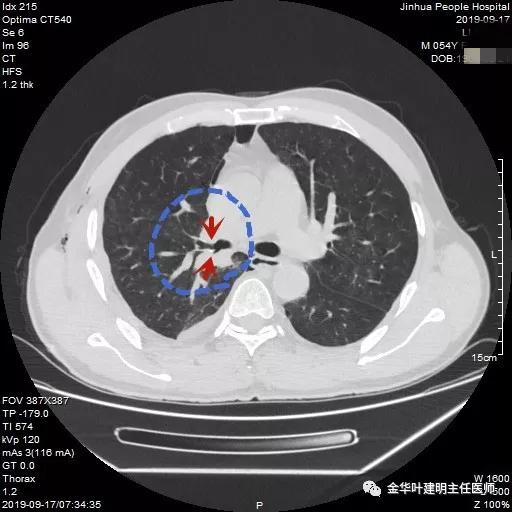

可见右中间支气管开口处新生物,堵塞管腔,明显是肿瘤,但因当时服用波立维与阿斯匹林双抗治疗,停的时间还不够,所以没有活检,而刷检没找到癌细胞。请我会诊时,我看了李某的胸部CT增强:

上图示上叶支气管通畅

上图示中间支气管起始处似乎还算正常

上图示中间支气管起始处以下3毫米处已经管壁增厚异常

上图示肿瘤堵塞管腔

上面各图示肿瘤位于肺门部,堵塞下叶及中间支气管

我们仔细看了增强CT,纵隔未见确切疑似转移的肿大淋巴结,这样的情况下,是不是再次气管镜活检,还是直接可以手术?当然从原则上来讲,应该再重新纤支镜检查,再活检以取得病理确诊后,再行手术。但个人以为,从影像及气管镜所见来讲,临床诊断已经可以确定为肺癌,而且中央型的以鳞癌为多见,当然也有的会是小细胞癌,不过小细胞癌一般很早就会有纵隔淋巴结转移,如果患者及家属理解,我认为从减少痛苦、节约经费、节省时间等方面考虑,直接手术也基本不会错的。当然所有的利弊与可能都要如实与患者及家属沟通,并征求他们的意见,最终李某及家属选择不再重新纤支镜检查与活检,要求直接手术。